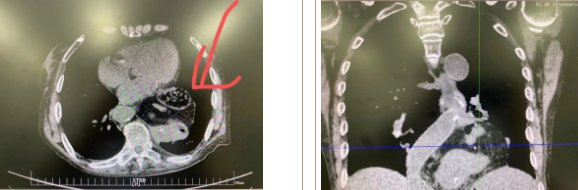

經(jīng)過三周充分準(zhǔn)備、院內(nèi)多學(xué)科會(huì)診及嚴(yán)謹(jǐn)?shù)男g(shù)前討論,西安國際醫(yī)學(xué)中心醫(yī)院胸科醫(yī)院李文海副院長帶領(lǐng)團(tuán)隊(duì)為一位82歲高齡,多臟器功能不全且合并腫瘤患者成功實(shí)施“巨大膈疝修補(bǔ) 抗返流手術(shù)”。

據(jù)了解,患者多年來進(jìn)食后出現(xiàn)惡心、嘔吐,卻未到醫(yī)院進(jìn)行檢查。3個(gè)月前患者突然出現(xiàn)無尿,全身腫脹等情況才前往就醫(yī),卻遭多家醫(yī)院拒收,輾轉(zhuǎn)來到我院就診。檢查發(fā)現(xiàn)患者已患宮頸癌、進(jìn)而引起腎后性腎衰、同時(shí)合并膈疝、出現(xiàn)泌尿道感染,病情及其復(fù)雜。

經(jīng)泌尿外科積極救治,患者腎衰癥狀緩解,隨后轉(zhuǎn)入放射治療中心進(jìn)行宮頸癌根治性放療。放療期間,患者惡心、嘔吐癥狀逐漸加重,后期無法進(jìn)食,排除機(jī)械性腸梗阻和放療因素,考慮因長期膈疝加重引起,經(jīng)胸外科會(huì)診后轉(zhuǎn)入胸外科一病區(qū)準(zhǔn)備手術(shù)治療。

麻醉手術(shù)中心副主任丁倩為減輕患者術(shù)后不適,實(shí)施單腔聯(lián)合支氣管封堵插管,同時(shí)進(jìn)行了肋間神經(jīng)阻滯麻醉。術(shù)中發(fā)現(xiàn)患者膈疝巨大,食管和疝囊分界不清,部分胃組織和結(jié)腸疝已進(jìn)入胸腔。李文海憑借豐富的臨床經(jīng)驗(yàn),仔細(xì)辨別解剖變異,有序完成分離、縫合、修補(bǔ)等一系列操作,胸外科穆強(qiáng)副主任醫(yī)師、劉歡住院醫(yī)師、麻醉手術(shù)中心團(tuán)隊(duì)通力配合,手術(shù)最終順利完成,患者安全返回胸外科監(jiān)護(hù)室病房。目前患者術(shù)后恢復(fù)良好,于近日準(zhǔn)備出院。